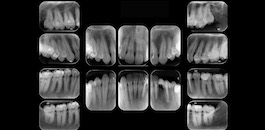

Exame realizado em apenas 17 segundos. Nosso equipamento permite a combinação de 9 diferentes tipos de arcadas, permitindo imagens nítidas e com altíssima definição.

Indicada para avaliação detalhada das estruturas interproximais.

Indicada para visualização detalhada das estruturas dento-alveolares.